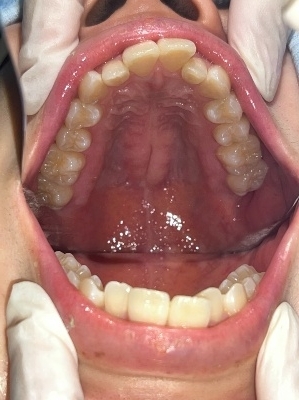

上顎

下顎